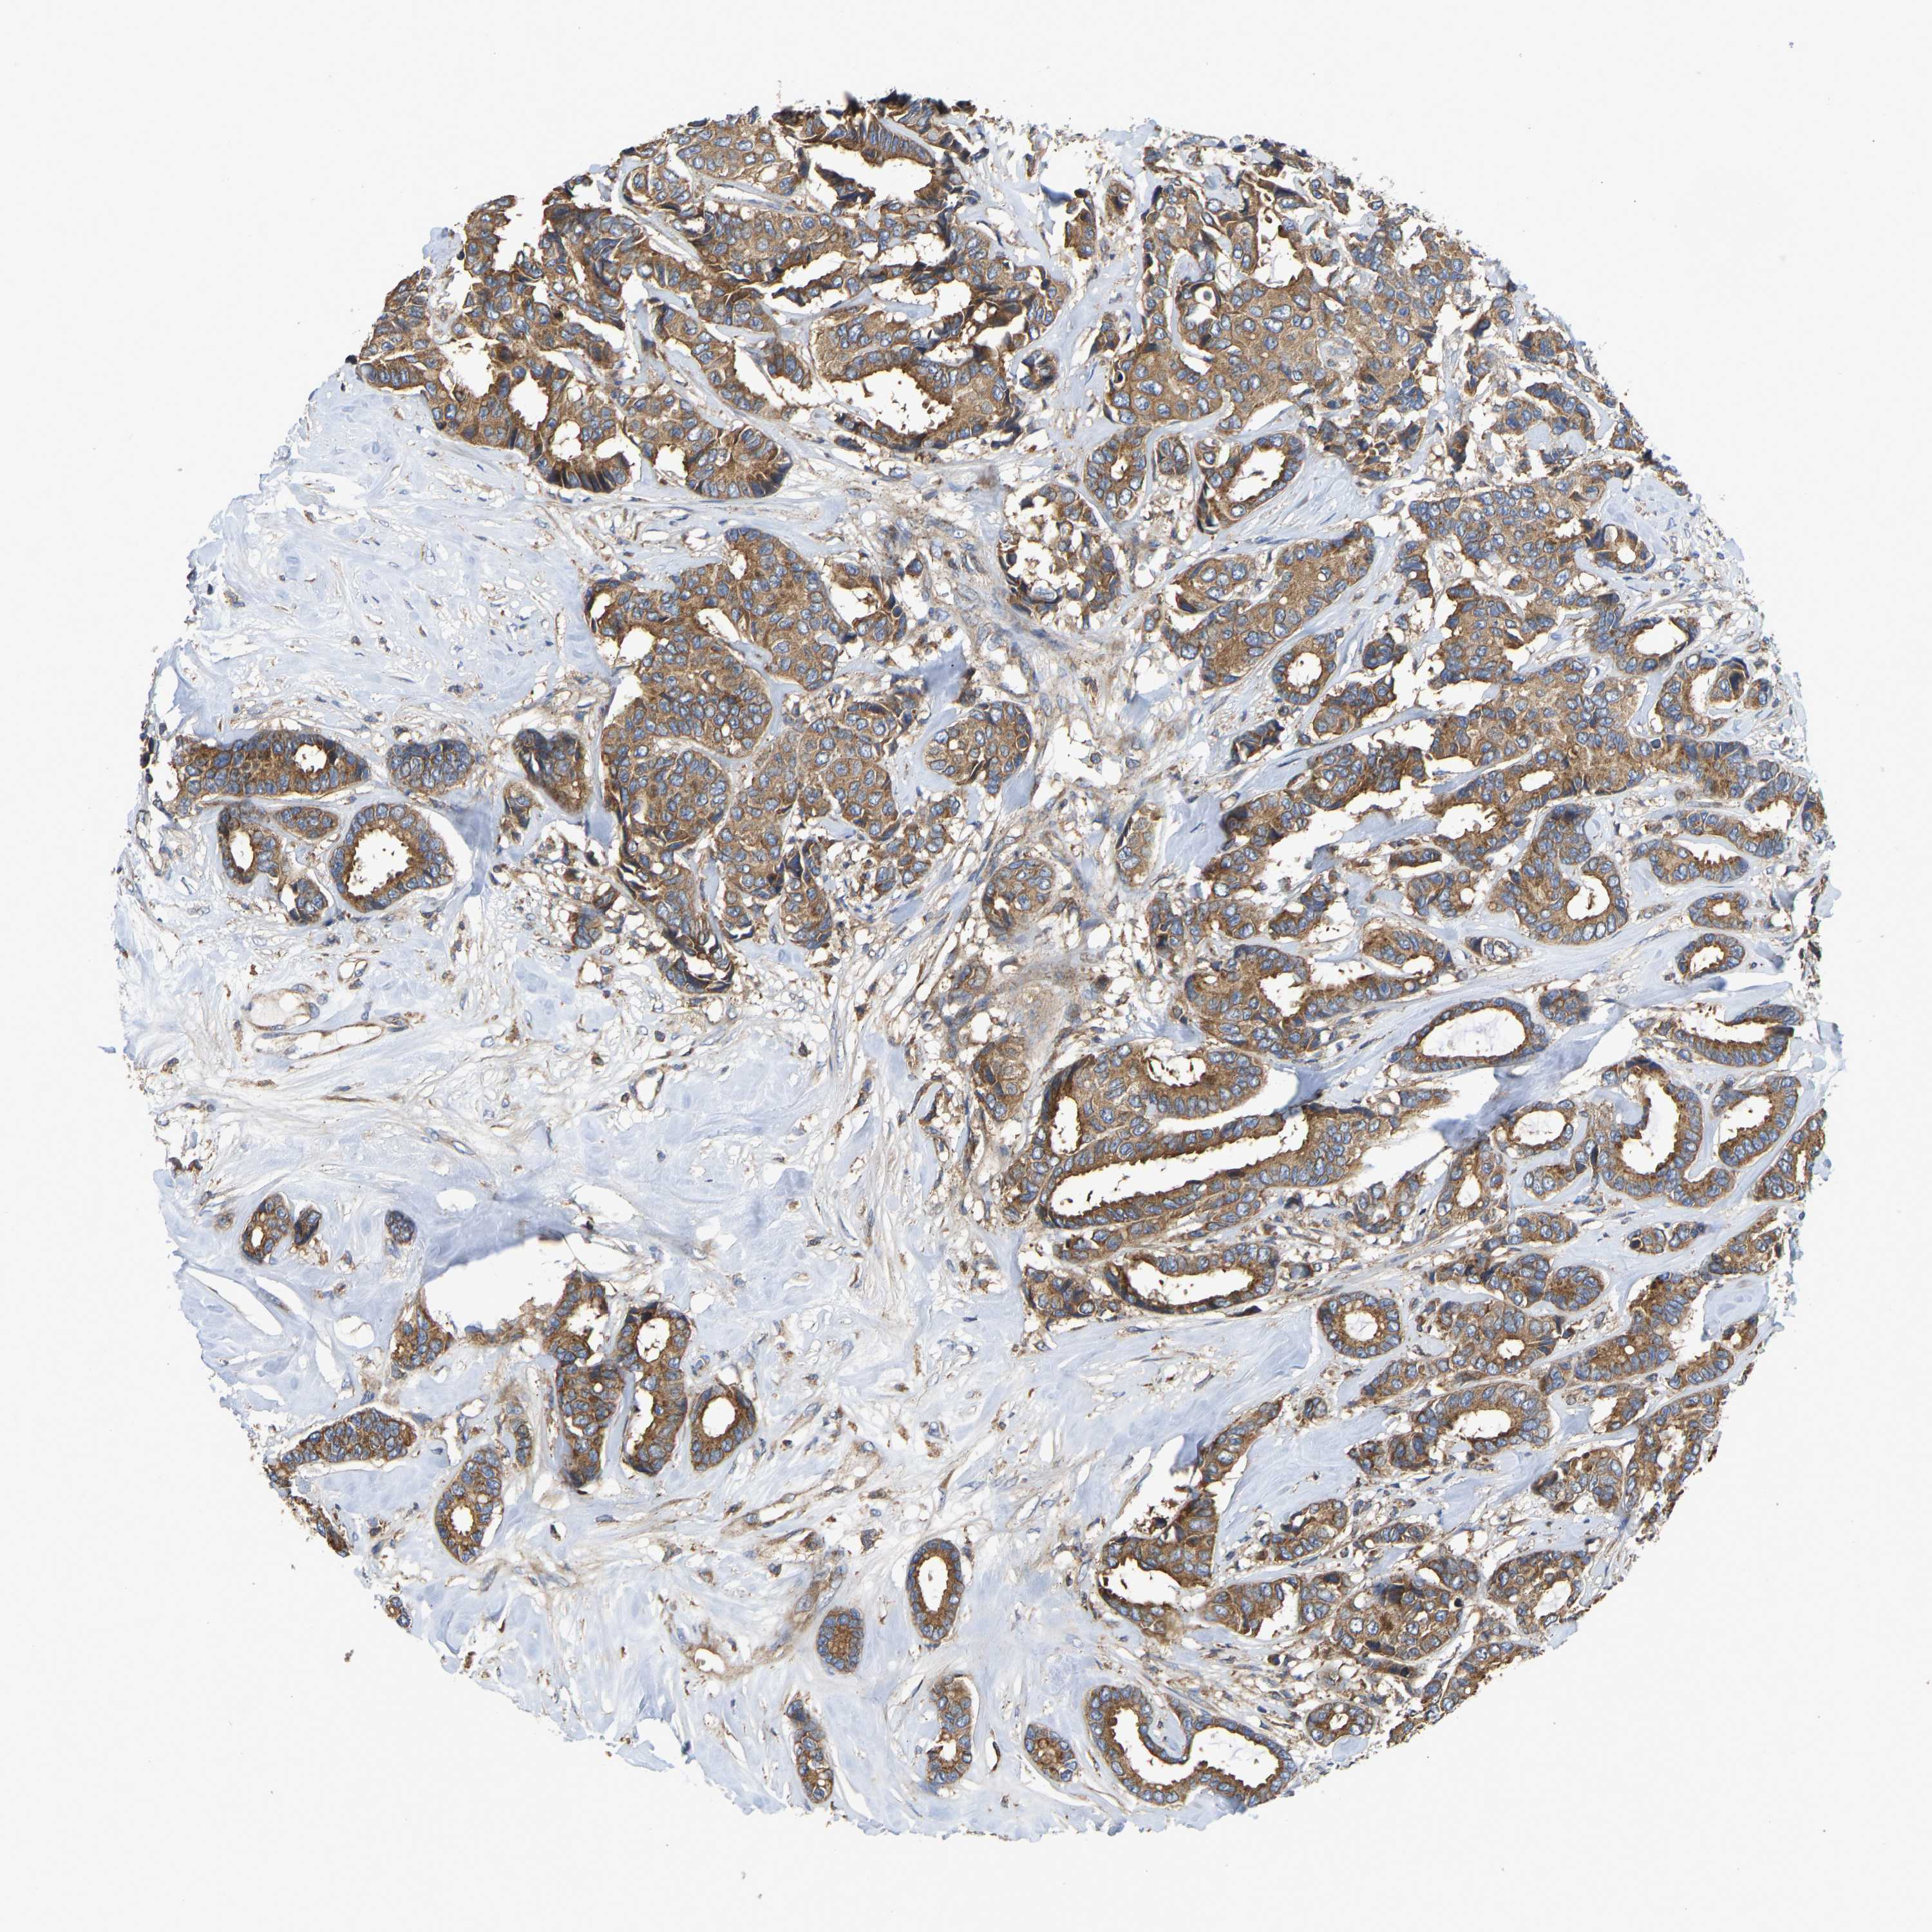

BRCA TCGA BRCA VALIDATION PROTEIN EXPRESSION